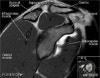

어깨 관절의 MRI 단면영상

- Coronal section

1) Supraspinatus, Inpraspinatus tendon

2) AC joint

3) Labrum(superior, inferior)

4) Biceps anchor, Inferior GHL, Axillary recess

5) GH joint cartilage

6) Osseous structure

7) Deltoid